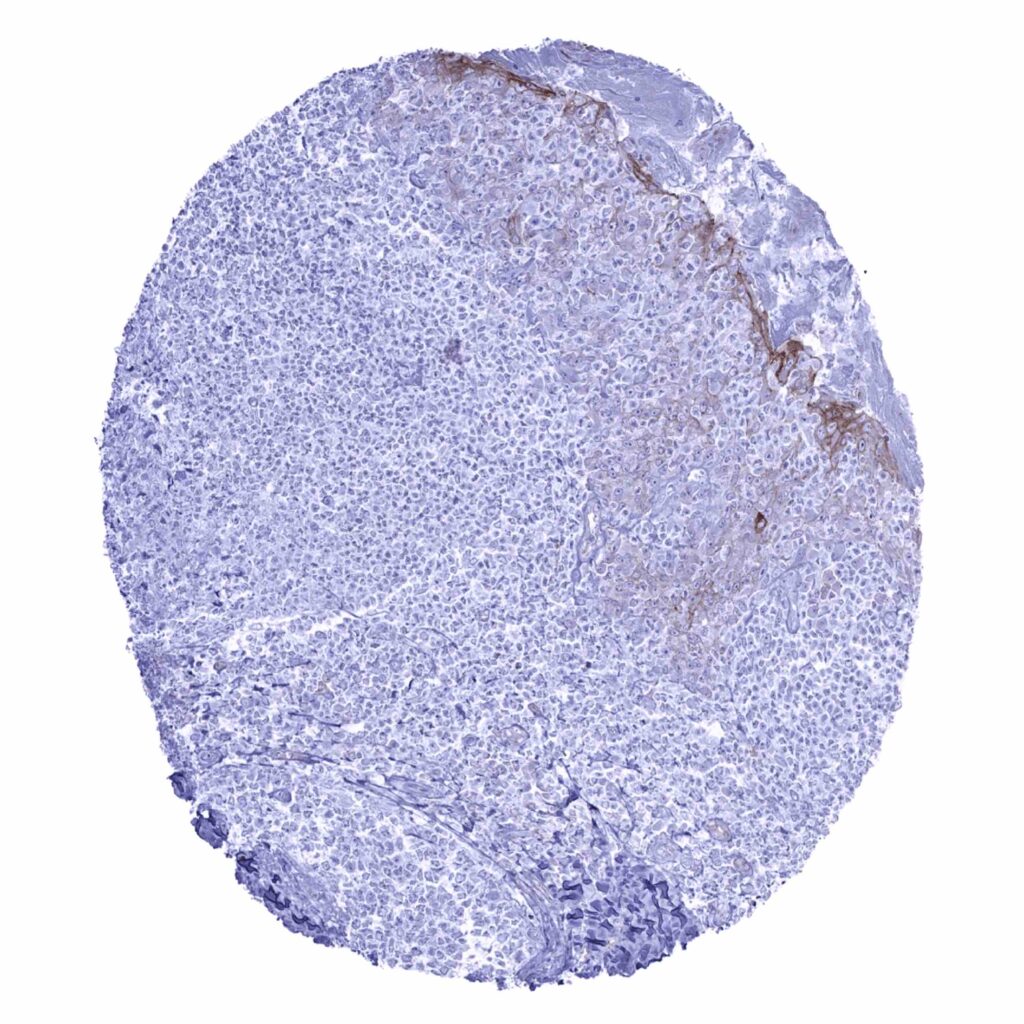

Lymph node – Significant occludin staining of endothelial cells (occludin immunohistochemistry)